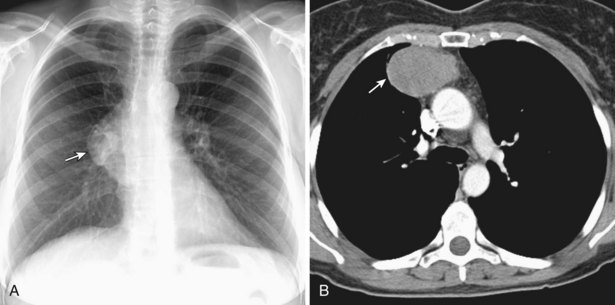

Диагностика лимфомы Ходжкина с помощью ПЭТ и КТ